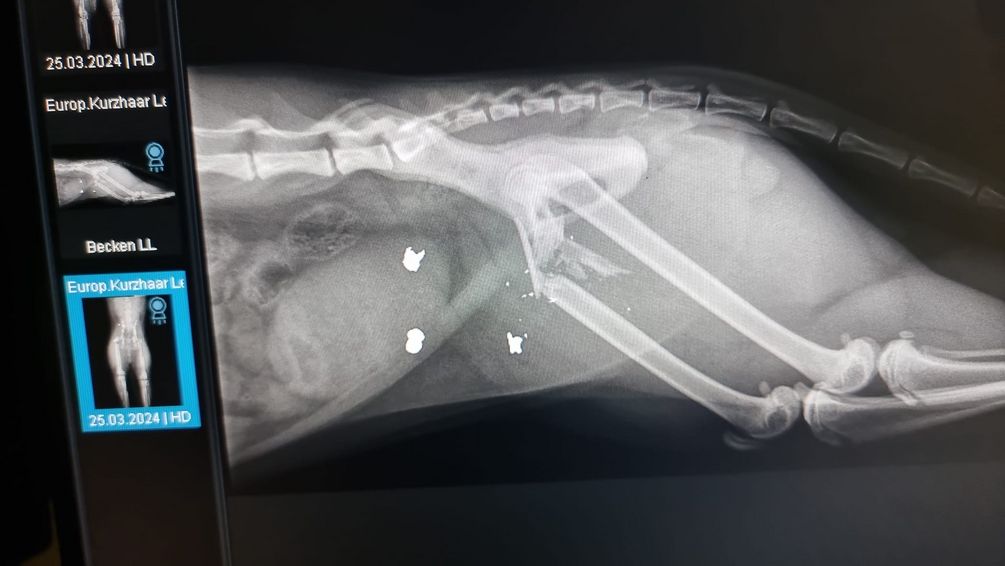

Kater "Leo" erlitt durch den Beschuss eine Trümmerfraktur des rechten Hinterlaufes und musste von einem Tierarzt behandelt und operiert werden. Der Täter konnte noch nicht ausfindig gemacht werden.